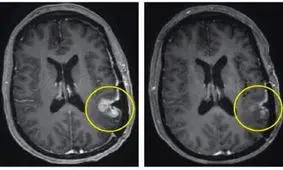

تومور مغزی مجموعهای از سلولهاست که بدون کنترل تکثیر شدهاند. تومور ممکن است در هر ناحیهای از مغز ایجاد شود. برخی از این تومورها خوشخیم هستند. یعنی به کندی رشد میکنند، به بافتهای مجاور حمله نمیکنند و پس از برداشتن دوباره ظاهر نمیشوند. از طرف دیگر تومورهای بدخیم نگران کنندهتر هستند، زیرا سرطانی هستند.

تومور مغزی نه تنها بر طول عمر افراد مبتلا اثر میگذارد بلکه میتواند به طور قابل توجهی کیفیت زندگی این افراد را نیز تحت تاثیر قرار دهد.